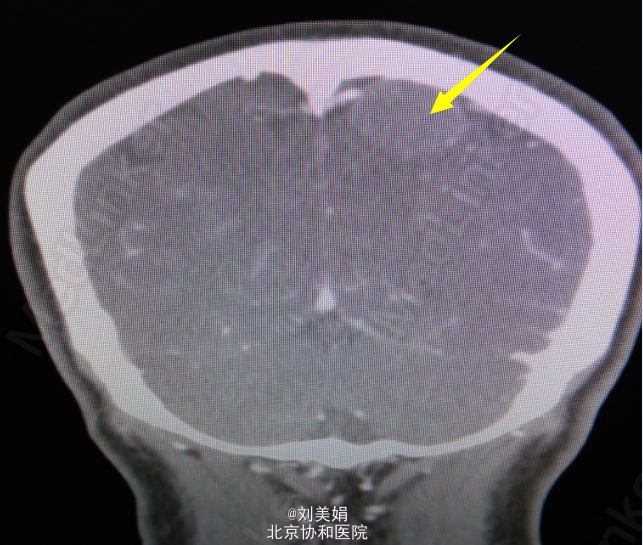

头增强CT:平扫图象显示:左侧顶部见一圆形略高密度影,边缘光整,边界清晰,大小约28.2mm×23.7mm,CT 值 68.2Hu,其内未见钙化,周围脑回受压、塌陷,脑室系统无扩大,脑沟裂未见增宽。中线结构未见明显移位。 增强图象显示:病灶明显均匀强化。CT 值为 92Hu,密度均匀,边缘清晰。右侧筛窦密度增高。